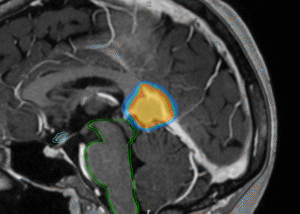

- Target delineation: The MRI +/- angiogram are registered with CT and then a member of the team defines the volume to be treated and normal structures.

- Planning: The physics team produce the plan and then perform various safety checks prior to treatment. This is complex and can take between 2 and 4 weeks. Most treatments are planned using 3-4 arcs which rotate around the centre of the lesion.